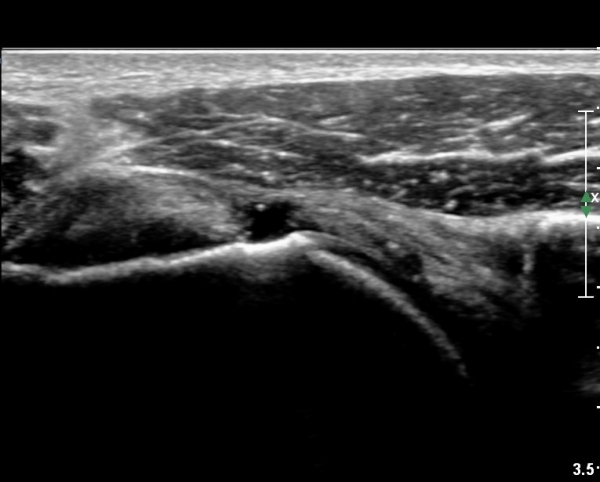

ÆÈÀ» ¿ÜȸÀüÇϸ鼭 °üÂûÇÏ´Ï °ß°©ÇÏ±Ù°Ç ÆÄ¿­ÀÌ ¶Ñ·ÈÇÔ(»çÁø 2, 3).

°ß°©ÇÏ±Ù°Ç »óºÎ Á¾´Ü¸é°Ë»ç¿¡¼­ °ß°©ÇϱٰǠ ÆÄ¿­ÀÌ ¶Ñ·ÈÇÔ(»çÁø 4, 5).